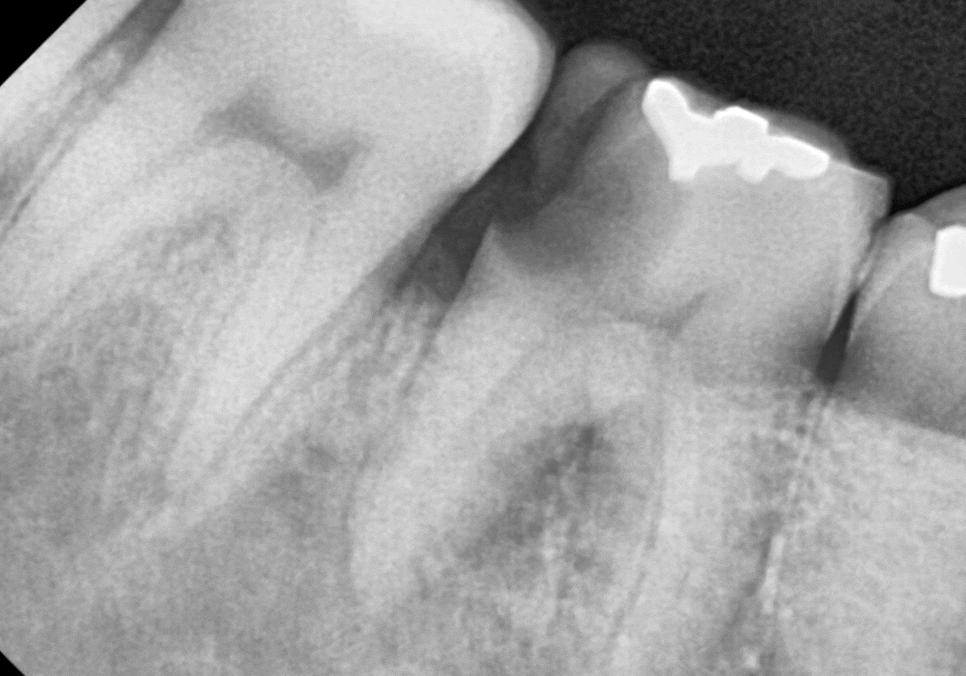

얼마 전 오른쪽 아래 어금니 통증으로

내원하신 환자분이 계셨어요.

입안을 자세히 살펴보니,

어금니(#46)의 윗면이 깨져,

그 틈으로 음식물이 꽉 끼어 있었어요.

음식물에 눌려있던 잇몸은 빨갛게 부어올라

살짝만 건드려도 피가 날 정도였어요.

엑스레이와 3D CT로

정밀 검사를 진행해 보니,

치아 사이에서 시작된 충치가

치아 내부 상아질을

이미 광범위하게 녹인 것을 확인할 수 있었습니다.